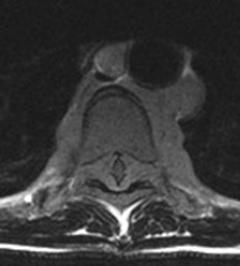

Intense homogeneous contrast enhancement

DWI Hyperintense

Periventricular lesions

Hyperdense lesion on nonconstast CT

Corpus callosum involvement